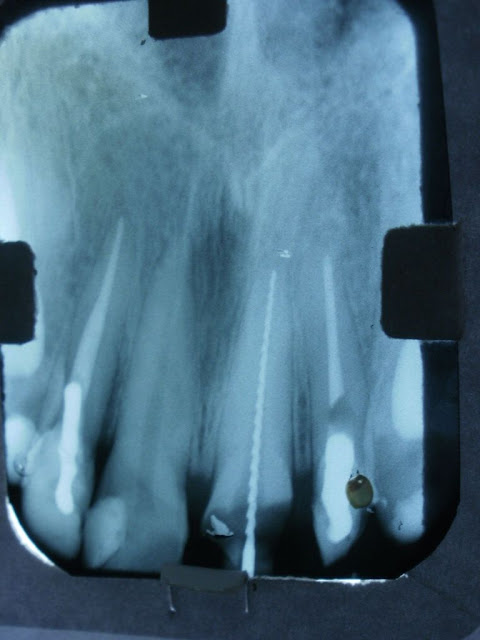

(4663) Endodontia - Canal de Incisivo Central Superior

Radiografia de Medição (Odontometria)

Nova medição após fratura da coroa durante o tratamento.